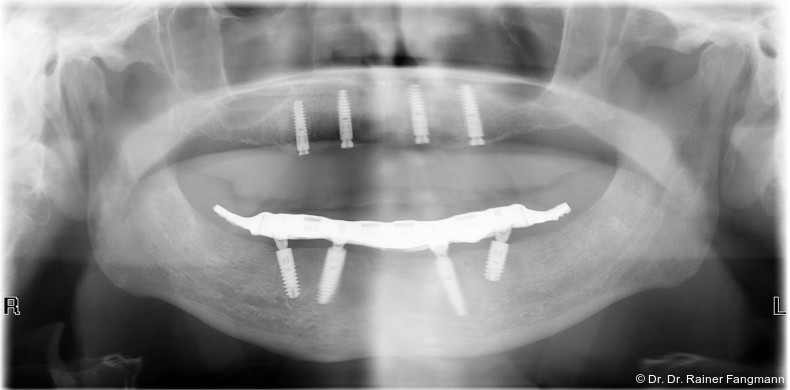

Die Fragestellung zur Implantatanzahl im Oberkiefer oder Unterkiefer ist oft sehr patienten- und behandlerspezifisch zu betrach-ten. Für Kostenträger ist die Frage oft von übergeordneter Relevanz. Für den Praktiker stellt sich die Frage nach der Umsetzbarkeit. Zudem sind auch das Knochenangebot und dessen Qualität für die Anzahl der Implantate und auch der Implantattypus maßgebend. Folgender Beitrag zeigt ein Fallbeispiel mit drei Implantaten, sechs Jahre in situ.

Ein immer viel diskutiertes Thema ist die Implantatanzahl beim All-on-X-Konzept. Diese ist von vielen Faktoren abhängig. Zu nennen sind der Implantattyp, der Implantatdurchmesser und die Implantatinnengeometrie. Im Weiteren sind die Knochenqualität und -quantität zu betrachten. Auch spielt die Gegenbezahnung zum All-on-X-Kiefer eine entscheidende Rolle, sodass hier keine einheitliche Linie für den Oberkiefer erkennbar ist. Es gelten in der Regel vier bis sechs Implantate als ausreichend. Im Unterkiefer sind es in der Regel vier. Wie dargestellt, reichen bei diesem Implantatsystem auch drei Implantate aus.